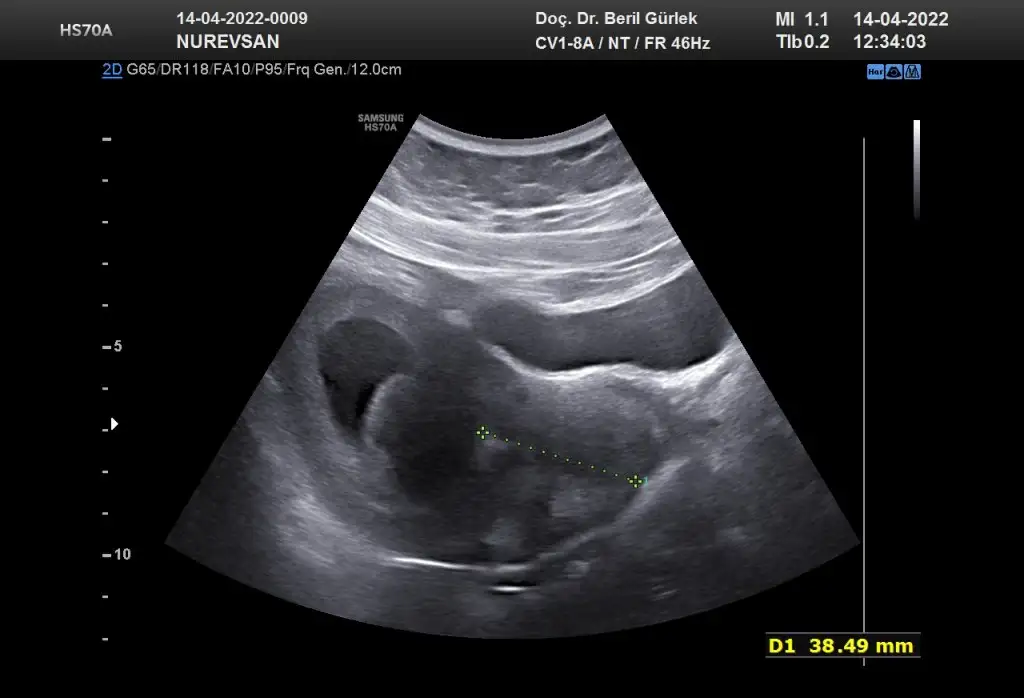

Ay ne güzel başlık banada tahmın edebılır mısın😊🤗 burda 8 haftalık karından bakıldı sımdı 10 haftalıgım 2 hafta sonra gidicem doktora bır tahmınde bulınabılır mısın

Burada 8 haftalık karından canım